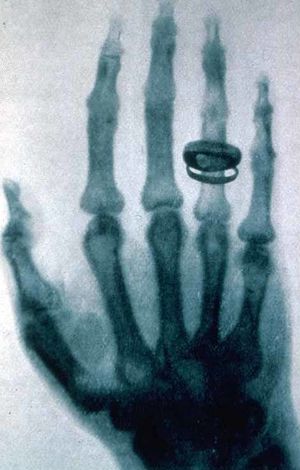

يد بخاتم: طبعة لأول آشعة سينية "طبية" أخذها ڤيلهلم رونتگن، وكانت ليد زوجته، وقد أخذها يوم 22 ديسمبر 1895، وقدمها إلى پروفسور لودڤيگ تسـِندر بمعهد الفيزياء، بجامعة فرايبورگ، في 1 يناير 1896[1][2]

صورة آشعة سينية (راديوگراف) أخذها رونتگن ليد ألبرت فون كوليكر.

كان رونتگن يجري تجارب على أنبوب كروكس وهو أنبوب تفريغ كهربائي ذو ضغط منخفض تتولد فيه الأشعة المهبطية نتيجة تطبيق فرق كمون عالٍ بين مهبط ومصعد، نموذجاً مطوراً منه يستخدم في الحقيقة لتوليد الأشعة السينية. فقد وجد رونتگن أن أملاح الباريوم الموضوعة بجانب الأنبوب تتألق كلما أغلق دارته الكهربائية الخاصة بأنبوب التفريغ، وأن هذا الأمر لا يتوقف حتى بعد تغطية الأنبوب بغطاء أسود كتيم. وقاده تفكيره إلى أن ضرباً من الأشعة أطلق عليه اسم الأشعة السينية ـ لجهله بطبيعتها ـ يصدر عن الأنبوب ولم يشأ لتواضعه أن يطلق على هذه الأشعة الاسم الذي عرفت باسمه فيما بعد. وطفق رونتگن يعمل ليل نهار لكشف خصائص هذه الأشعة فوجد أنها تنتشر وفق خطوط مستقيمة تماماً كالأشعة الضوئية، كما اكتشف أنها تؤين الهواء الذي تمر فيه. ودرس مقدرتها على النفوذ في الأجسام المادية فوجد أن هذه الأشعة تخترق بعض المواد كاللحم، وأنها تعجز عن اختراق مواد أخرى كالعظم وهكذا فقد اكتشف أنه يمكن تصوير توزع عظام يد زوجته وتسجيلها على لوح تصوير.

أحدث اكتشاف رونتگن للأشعة السينية ضجة في الأوساط العلمية والطبية مما خوله لنيل أول جائزة نوبل في الفيزياء عام 1901، ولم تمض إلا بضعة شهور حتى استخدم الأطباء هذه الأشعة لتصوير الكسور وساعدهم ذلك على جبر كسور العظام.